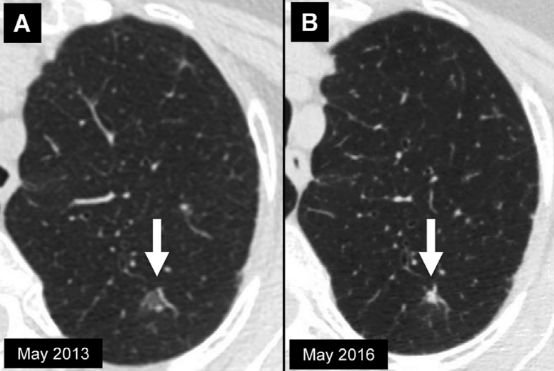

右肺上叶磨玻璃结节 (箭头) 的时间顺序扫描。结节的平均直径为A、13mm,B、14mm,C、18mm。当我们将最早的图像与最新的图像进行随访,测量应在结节中心层面上进行,不一定和上次检查的解剖学层面相同。